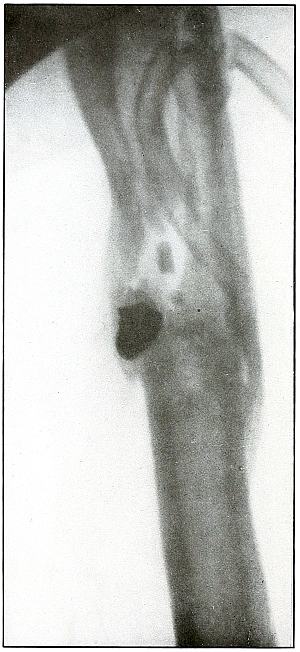

Plate 10.

[Pg 31]

Rifle—Plate 10.

UPPER EXTREMITY.

Gunshot Fracture of the Left Humerus,

with Lodgment of the Missile.

Wound of entrance, anterior surface of upper third of the arm.

Wound of exit, none.

The shadow of the missile shows by its distinct outline and normal

diameter at the tip that the missile lies on the side near the plate;

the shortened length of the projectile indicates that the long axis

lay in an acute angle with a perpendicular to the plate.

The irregular outline of the base of the shadow and the fact of

lodgment shows that the missile was deformed and that it was

incidentally retarded in velocity by ricochet, so that its penetrating

force was not sufficient to carry it through the arm.

The fragments of bone are large and the wound is of the same character

as might have resulted from a shrapnel ball, for the normal ballistic

conditions of the latter simulate the conditions that produced the wound.

The drainage tubes seen in the plate indicate infection.

The conventional treatment in such cases is drainage and other

management of the infection without formal search for the projectile.

Results should be favorable.